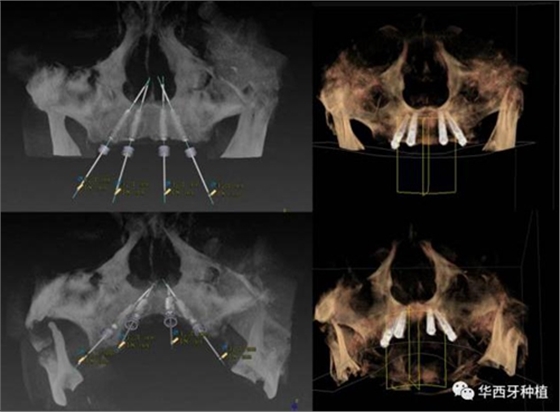

吳教授特別針對手術(shù)難度更大的all-on-four修復(fù)做了詳細(xì)的關(guān)于概念、設(shè)計(jì)、操作、修復(fù)的描述,首先是針對難度最大的手術(shù)環(huán)節(jié),就解剖、微創(chuàng)操作分別加以闡述。將他自己在臨床工作中的寶貴經(jīng)驗(yàn)分享給了大家。

對于傳統(tǒng)的all-on-four術(shù)式,吳教授加入了微創(chuàng)的指導(dǎo)思想,設(shè)計(jì)時(shí)同樣加入數(shù)字化三維重建與修復(fù)一體化設(shè)計(jì),增加了手術(shù)的可控性,同時(shí)極大減輕了患者的創(chuàng)傷程度,縮短了修復(fù)周期。

演講結(jié)束前,吳教授再次提到了數(shù)字化對口腔全口牙缺失種植修復(fù)一體化的重要性,構(gòu)建一體化的數(shù)字化種植修復(fù)流程,不僅能輔助手術(shù),更是簡化修復(fù)和確保遠(yuǎn)期療效的一把利器。